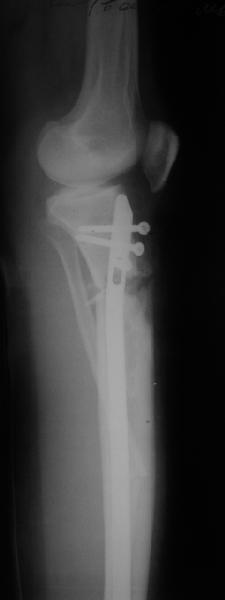

Продолжение обсуждения, начатого в октябре прошлого года (см. здесь) Наконец-то оперировали эту пациентку. Биопсию сделали - опухолевого ничего нет. Пока все участвовавшие в обследовании смежные специалисты и ортопеды сошлись, что это молокальная монооссальная фиброзная дисплазия. 20 марта наложили аппарат, сделали чрескожную остеотомию. К 3 апреля все докрутили. Сегодня заштифтовали. Начальные и итоговые снимки в приложении. Рекурвацию можно было еще немного больше устранить, и чуть кзади сместить диафиз. Но вроде и так ничего выглядит, по сравнению с тем, что было. Комментарии приветствуются.

Костной пластики не предполагалось, псчитали, что она избыточна. Остеотомия 2 недели назад проведена по курганской методике, т.е. через разрез 0,5 см. Вчера, когда штифтовали, уже зажившую рану над остеотомией не трогали.

Александр, по моему великолепно. Поздравлять будем, когда продемонстрируете консолидацию,функцию и внешний вид.

Вопрос: почему дистально только один винт? Предполагаете ли динамизацию?

АС> Вопрос: почему дистально только один винт?

Второй тут можно было сделать динамический, но отломок очень уж длинный, и ротационной подвижности даже без винтов не будет.

АС> Предполагаете ли динамизацию?

Если не успеет срастись месяца за два, то этот винт и уберем.

Есть клиновидный диастаз, контакт основных отломков на очень небольшой площади только в задненаружном отделе. Так что там скорее межотломковая дистракция, а не компрессия.